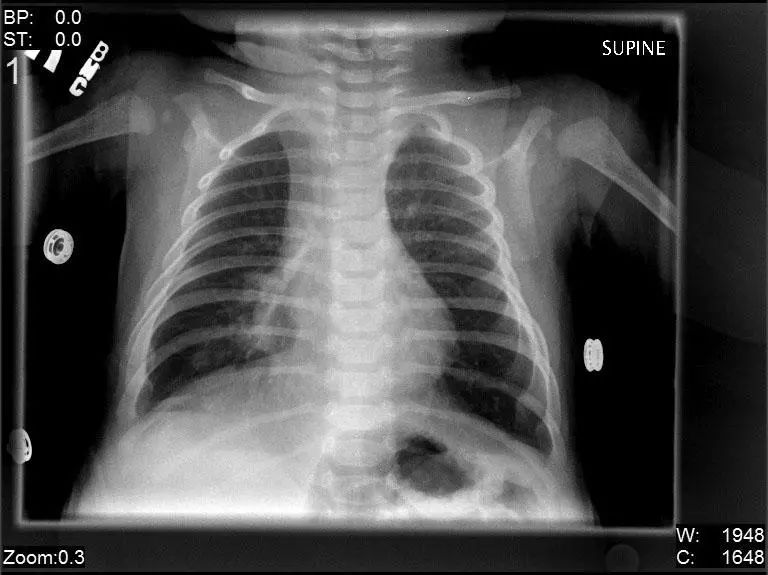

图1.2 细菌性肺炎。双肺下叶肺炎患者影像。